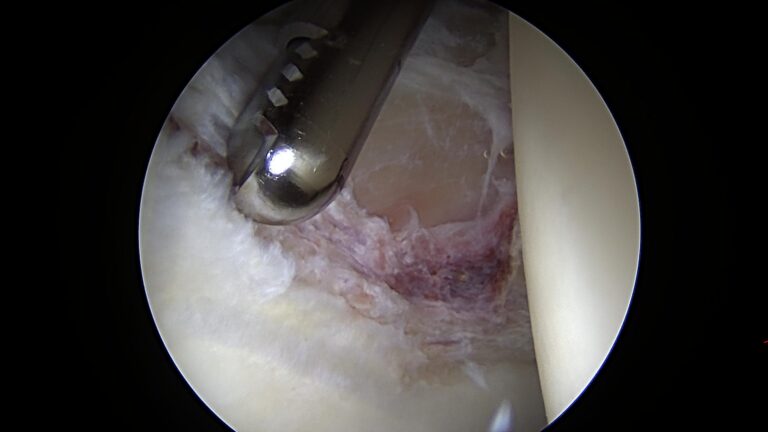

In the above arthroscopic video of the hip, the probe is demonstrating an unstable flap of cartilage immediately adjacent to the labrum, which is underneath the probe. The probe then pushes on the labrum to demonstrate its instability as well.

Additionally, note that there is also associated synovitis, as noted by the reddened appearance along the top of the screen.